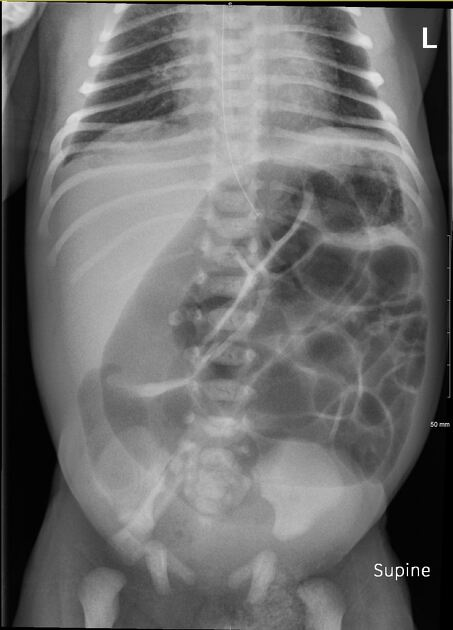

1. Neumatosis intestinal: La presencia de gas en la pared intestinal es un hallazgo clásico y altamente sugestivo de NEC.

2. Neumoperitoneo: La presencia de gas libre en la cavidad peritoneal sugiere perforación intestinal y es una indicación para intervención quirúrgica.[1][3-4]

4. Gas portal venoso: La presencia de gas en la vena porta es otro hallazgo ecográfico que puede estar presente en NEC, aunque su asociación con la necesidad de cirugía o muerte no es tan fuerte como otros hallazgos.[2][4]

El proceso de neumatización normal del intestino: a los pocos minutos del nacimiento se identifica aire en el estómago, a las 6-12 horas prácticamente todo el intestino delgado contiene aire, y a las 12-24 horas el aire ha llegado al recto.